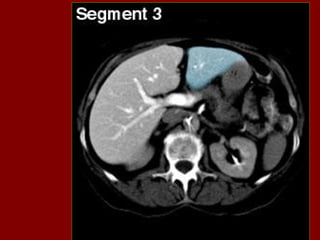

Ac Colo ascendente AP Nível de ar fluido do estômago Ao Aorta Az Veia ázigo CA Tronco celíaco cc Cartilagem costa! CD Ducto cístico CHA Artéria hepática comum CHD Ducto comum CL Lobo caudado fígado D Diafragma DBM Músculos para vertebrais De Colo descendente D2 Parte descendente do duodeno D3 Parte horizontal do duodeno E Esôfago FL Ligamento falciforme GB Vesícula biliar HA Artéria hepática Hz Veia IMV Divisão da veia mesentérica inf. C IVC Veia cava inferior LC Ramo esq. do diafragma LG Glândula supra-renal esq. LHV Veia hepática esquerda LIL Lobo inf. Esq. do pulmão LRV Veia renal esquerda LK Rim esquerdo LU Ureter esquerdo LL Lobo esquerdo do fígado MHV Veia hepática média P Pâncreas PA Antro pilórico do estômago